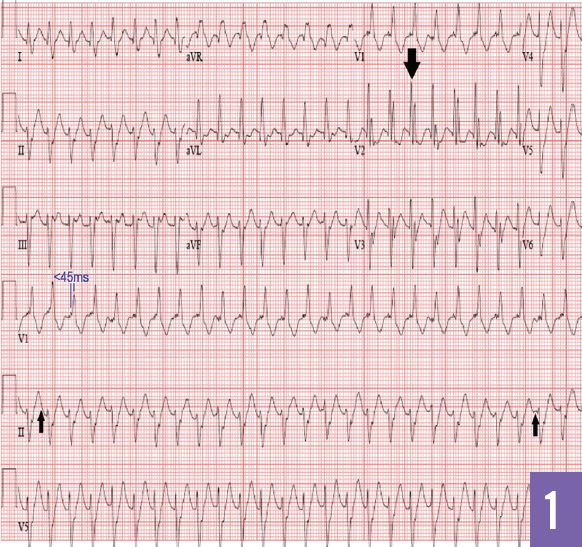

Meghana Halkar, MD; W.H. Wilson Tang, MD; Chadi Alraies, MD; Suzanne R. Lutton, MD; Martin N. Wiseman, MD

A 42-year-old man with no prior cardiac history presented to the emergency department after experiencing a syncopal episode a few hours after a 20-minute run.